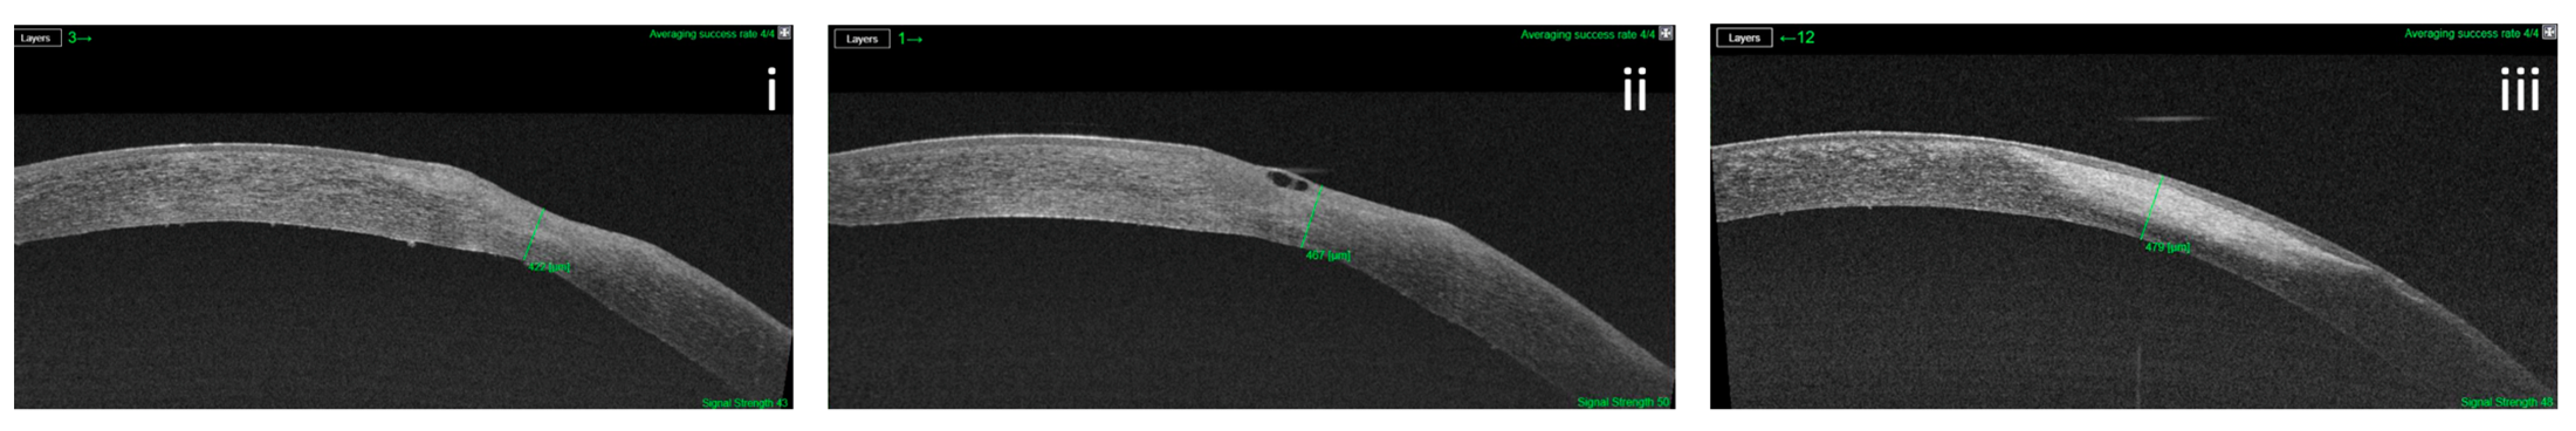

3.2. Corneal Thickness

This group differs in the OCT levels recorded in the three times (χ2(2) = 14.00; p = 0.001). Median (IRQ) OCT levels in the three time were 333 (305 to 382), 401 (381 to 423), and 454 (432 to 586), respectively. The subsequent post hoc analysis showed statistically significant differences in all three follow-up times considered, with an increase in OCT levels (p = 0.015 first time vs. 4 weeks; p = 0.016 first time vs. 8 weeks and p = 0.016 4 weeks vs. 8 weeks). (Figure 2).

Figure 2.

Variation of ulcer’s depth in a patient with post-herpetic NK treated with rh-NGF. The corneal thickness was calculated with OCT software at baseline: (i) 4 weeks, (ii) and 8 weeks (iii).